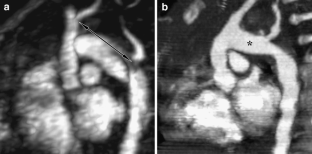

Fig. 7